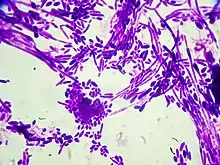

| Gram stain of Candida dubliniensis cells (1000-fold magnification) | |